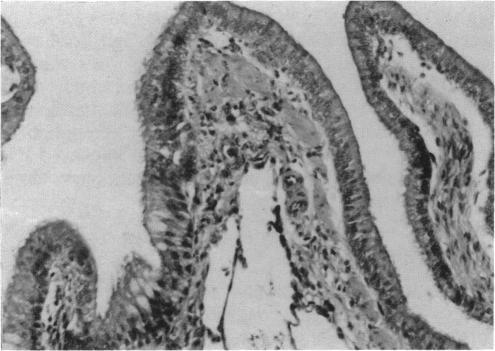

The objectives of this study were to describe the microscopic lesions in the respiratory tract of Fischer 344 rats as a result of 4- or 8-days exposure (6 hr/day) of 3 ppm MIC and to characterize the postexposure development of these lesions up to day 85. All rats survived the exposure regimen, although significant decreases in body weight and encrustation of the eyes, nose, or mouth were observed. During the first 15 days of postexposure, the rats were hypoactive and had increased respiratory rates. Male mortality was as high as 63%; only 5% of the MIC-exposed females died. The cause of death was interpreted to be respiratory compromise complicated by anorexia and probably dehydration as well. During the next 28 postexposure days, 48% of the male survivors died, while only 3% of the female survivors died. Throughout the 85-day postexposure period, body weight gains in the MIC-treated groups were consistently below control values. Inflammatory and squamous metaplastic lesions of the respiratory tract, observed the day following completion of either the 4- or 8-day exposure regimen, decreased in both frequency and/or severity in survivors of the 85-day postexposure period, indicating recovery from the cytotoxic and irritating effects of MIC vapor. The squamous metaplastic epithelium was replaced by regenerative epithelium beginning in the deeper portion of the respiratory tract.(ABSTRACT TRUNCATED AT 250 WORDS)